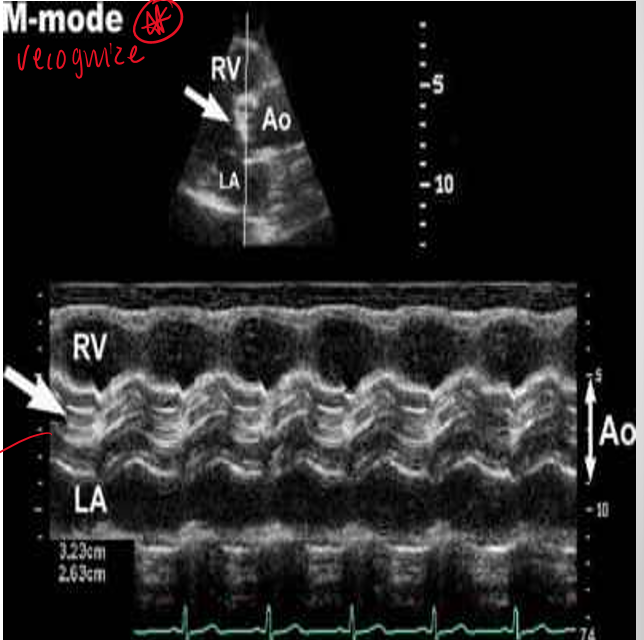

what does bicuspid ao valve appear like on m mode? **

eccentric line closure